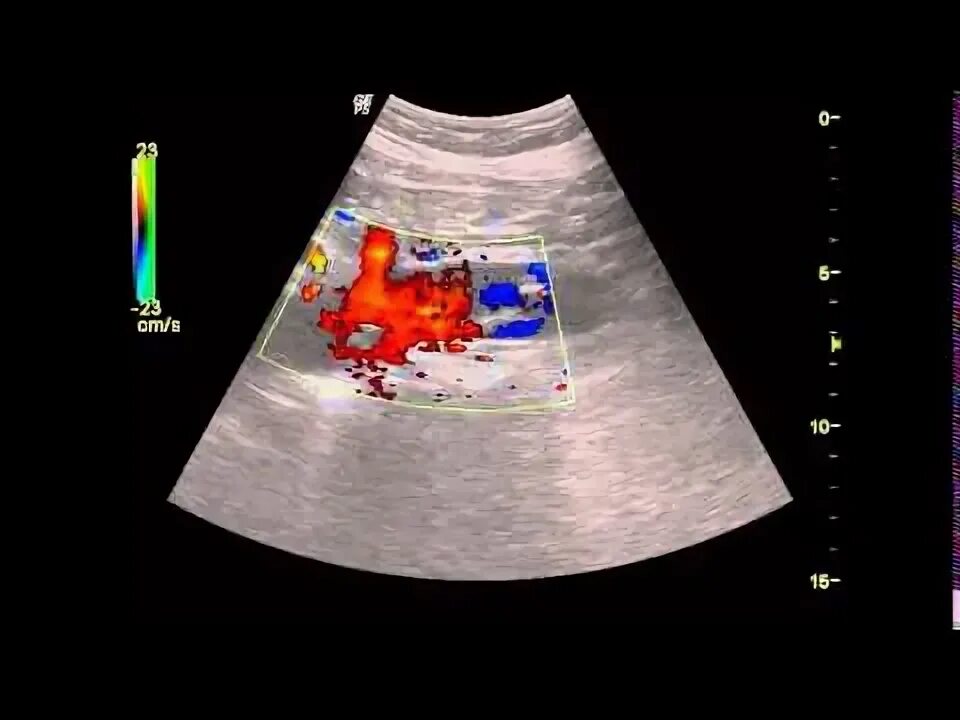

Дегенеративные изменения стенок аорты